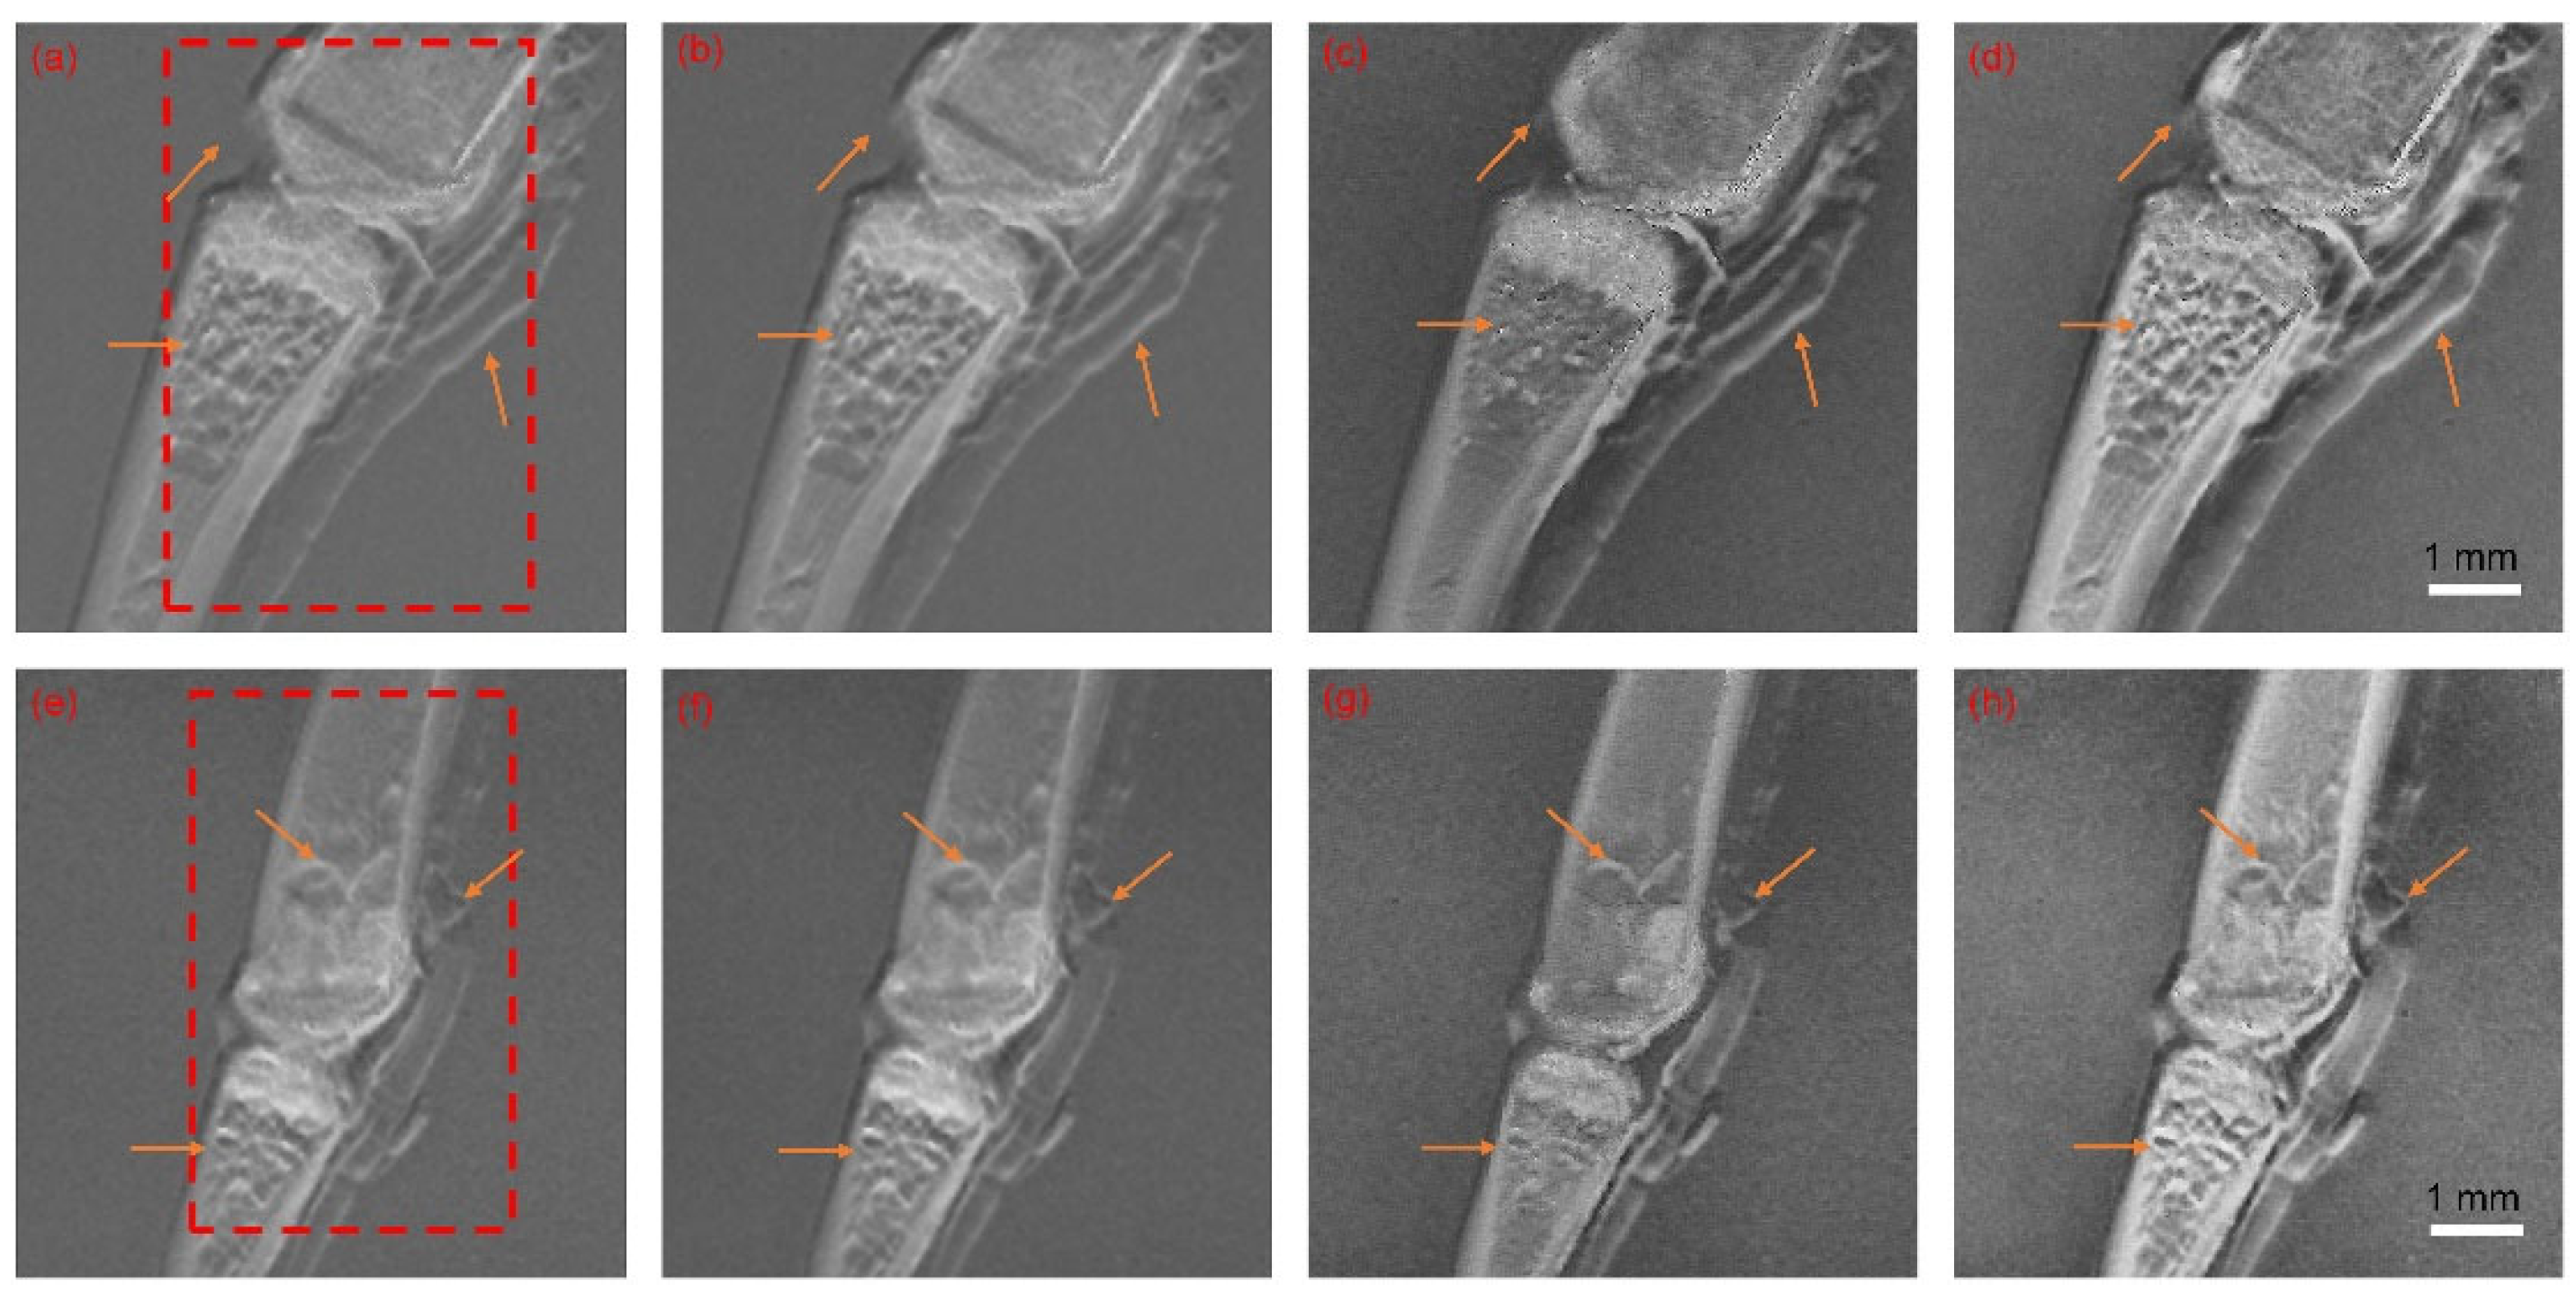

- the proposed NSCT-SCM image fusion scheme was applied to XGI data of frog toes and compared with current fusion methods in the XGI fusion field, exhibiting state-of-the-art performance.